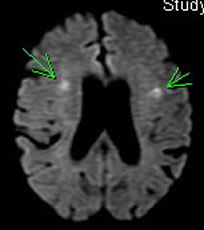

| 拡散強調画像 | 最近 3ヶ月以内に起こった病変が白く光る撮り方 |

MRI

GEヘルスケア製

超伝導磁石式全身用MRI装置(SIGNA Creator 1.5T MRI)を導入。

MRI検査では強い磁石と特殊な電波により、寝ているだけで全身の様々な断面の撮影が可能な装置です。

造影剤なしでも血管画像が撮影でき、放射線も使わない検査のため、どなたでも安心して検査を受けていただくことが可能です。

(ただし心臓ペースメーカーや人工内耳が入っている方は検査をお受けできません。)

また、CT検査よりも早期の脳梗塞の発見にも強いという特徴があります。